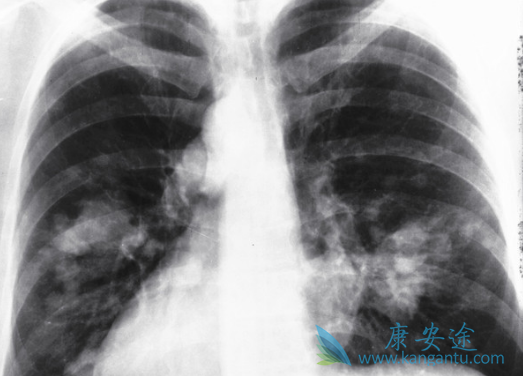

近期,一项临床试验研究了吉非替尼(GEFITINIB)对非小细胞肺癌患者免疫功能的影响,研究发现,EGFR-TKI靶向治疗非小细胞肺癌,可明显改善患者的免疫功能,临床疗效较好,不良反应发生率低。该文章发表于《中国临床药理学杂志》上。该研究旨在观察表皮生长因子受体酪氨酸激酶抑制药(EGFR-TKI)吉非替尼在靶向治疗非小细胞肺癌(NSCLC)中对患者免疫功能的影响。

研究者们入选65例服用吉非替尼(GEFITINIB)治疗的非小细胞肺癌患者,所有患者均口服吉非替尼250mg,连续服用30d。观察治疗前1周、治疗后1,3,6个月T淋巴细胞亚群和自然杀伤(NK)细胞的变化,观察治疗后的临床疗效及不良反应发生情况。结果显示,治疗后客观缓解率为75.38%。

治疗后6个月,患者的CD3+、CD4+、CD8+、CD4+/CD8+、NK细胞分别为(74.14±7.03)%,(43.15±6.02)%,(27.93±4.88)%,(1.98±0.32),(25.34±3.97)%,与治疗前相比,差异有统计学意义(P<0.05)。吉非替尼(GEFITINIB)治疗后,白细胞介素-2、肿瘤坏死因子-α、干扰素-γ、白细胞介素-4、白细胞介素-5、白细胞介素-6分别为(56.67±10.69),(63.71±10.54),(59.14±10.87),(27.47±7.12),(43.21±14.21),(68.98±12.56)ng·L-1,与吉非替尼治疗前相比均得到显著改善(P<0.05)。不良反应率为12.31%。